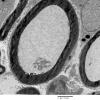

4 AXONAL DEGENERATION

3 Electron Microscopy